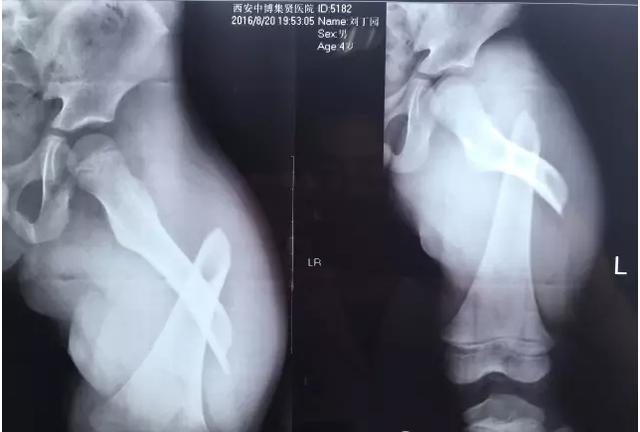

專家表示,大部分骨折是跌倒引起的,最多見(jiàn)的就是骨質(zhì)疏松性骨折,主要包括橈骨遠(yuǎn)端、肱骨近端、胸腰椎骨折和髖部骨折。

“許多人跌倒后的第一反應(yīng)是手撐地,導(dǎo)致摔倒的力量經(jīng)手腕傳導(dǎo)至前臂,從而形成橈骨遠(yuǎn)端骨折?!北本┓e水潭醫(yī)院新街口院區(qū)創(chuàng)傷骨科副主任醫(yī)師王陶說(shuō),如果是髖部骨折,對(duì)高齡老人而言,風(fēng)險(xiǎn)和危害更大。

老年人發(fā)生骨折后該如何治療?“對(duì)于一些高齡老人,骨折后可能并不適合做手術(shù)、打石膏,特別是需要臥床的,保守治療期間要注意定期翻身、加強(qiáng)營(yíng)養(yǎng)和適當(dāng)康復(fù)訓(xùn)練,避免出現(xiàn)褥瘡、肺炎、下肢靜脈血栓等。”上海市老年醫(yī)學(xué)中心骨科主任醫(yī)師林紅說(shuō)。